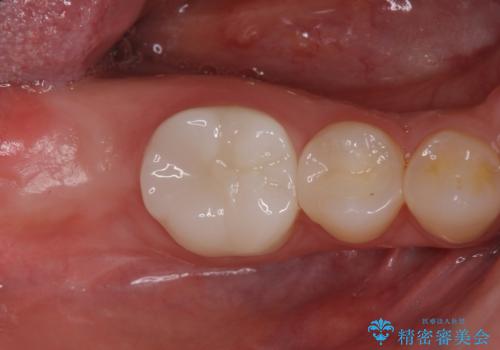

- 右下の奥歯がない状態でしばらく過ごされていた方です。

インプラント入れて噛めるようにしたいとのことだったため、治療を行います。

向かい合わせになる歯が歯茎と噛んでいるため、歯茎の厚みも調整していきます。

今回はかぶせ物の高さを確保するために、少し顎骨を削り、歯肉の厚みも薄くしました。